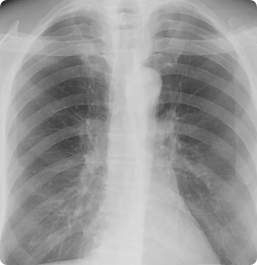

Lung cancer and coronary disease are worldwide leading killers and early detection is key to improving outcomes. CAC affects 20 million Americans annually, yet over half of incidental findings go unreported.12,13 Lung cancer is the leading cause of cancer death and nodule search is burdensome, and vessels can obscure findings, delaying diagnosis. Findings are time-consuming to compare over time, segment, and quantify. In addition, exploding imaging volume and radiologist shortages and burnout are at a breaking point.

ClearRead CT with Clear Visual Intelligence provides an unimpaired view of the chest for efficient and accurate detection of cardiothoracic diseases. The full suite of tools detects, segments, and measures nodules, compares findings with prior exams, quantifies CAC, and automatically integrates with the radiology report. ClearRead CT is a natural addition for opportunistic CAC and nodule detection or as part of a lung cancer screening program. Detect 29% more nodules and read 36% faster.2,14